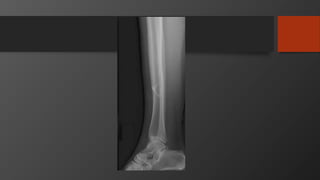

Imaging

• AP, Lateral

• Mortise view

• CT scan

• Especially posterior malleolus